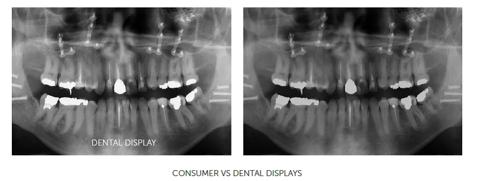

An image shown on a dental display (left) offers more contrast and more detail compared to images shown on non-medical consumer displays (right).

With dental monitors, important anatomical structures in dental images are more visible, compared to consumer displays. This makes it easier for dentists to detect dental pathologies.